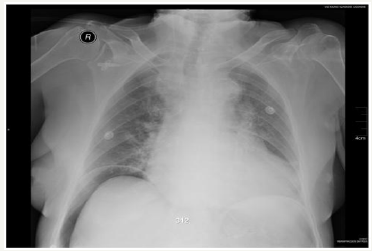

Haematin and not much fresh blood were seen in the stomach. Pylorus and duodenum were without any changes. 10ml of sol. Adrenaline (0.1 percent) was injected to the stomach antrum beside the minor curve to stop the bleeding. The bleeding has stopped. After that the patient was treated conservatively. Her condition was stable; she had no pain of abdomen. Next day the patient was suspected to have pneumonia due to the occurring failure in the respiratory system (her saturation decreased to 88 percent without oxygen and the respiratory rate has increased to 22 times per min). Chest x-ray was done. It denied pneumonia diagnosis but revealed free air in peritoneal cavity (Figure 1).

The chest x ray was repeated but the findings were the same. During the physical examination patient abdomen was a little distent, painful around the umbilicus, but without any signs of peritonitis. Blood test has showed: WBC – 37.1 x109/l, CRP - 18.0mg/l. There was no way to eliminate hollow viscera perforation. The urgent laparotomy was done. A lot of air in peritoneal cavity was found during the operation (the gas went outside from the peritoneal cavity with pressure after the incision of abdominal wall was done). Small haematoma and infiltration were seen in the minor curve of the stomach (probably it was the zone of injected Adrenaline during FEGDS). No hollow viscera perforation was found. Stomach and duodenum were mobilised and 2000ml of physiologic liquid were poured to the abdominal cavity. The air was insufflated through the nasogastric probe. No air bubbles were seen. Peritoneal cavity was drained and incision of abdomen was sutured. The patient was treated in ICU next few days. The patient hemodynamic was stable, her respiratory system function got better. Next day after the surgery patient’s WBC has decreased to 16, 9 x109/l, later to 9,3 x109/l. Haemoglobin has rised to 104g/l, later to 132g/l. Twelve days after the surgery patient was discharged from the hospital (Figure 1).

Figure 1:Chest x-ray showing pneumoperitoneum.

Plain or lateral decubitus abdomen or chest x ray can help diagnose pneumoperitoneum: it shows free air within the peritoneal cavity under the diaphragm [2], as it was in our case. Non-surgical pneumoperitoneum in most cases is founded accidentally: when for some reasons chest x ray is done (i.e. to diagnose pneumonia) [5]. It is important to mention that pneumoperitoneum is visible on abdominal x-ray just in 85-89 percent of the cases with a rupture of a hollow organ [5,13]. When perforation is suspected but pneumoperitoneum is not visible on abdominal x-ray, a computer tomography may be done: it can reveal free air in peritoneal cavity in up to 95 percent of cases with a ruptured hollow viscerus [5]. Furthermore, strict attention must be given evaluating x-ray for pseudopneumoperitoneum: particular pathologies (such as overdistension of hollow viscera, undulant configuration of the diaphragm, interposition of the colon hepatic flexure between the right lobe of the liver and the diaphragm, etc.) can simulate pneumoperitoneum [10].